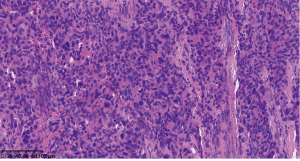

Subsequently, 18F-FDG and 68Ga-DOTATATE PET-CT scans were conducted to evaluate the presence of multifocal lesions or distant metastases. The whole-body maximum intensity projection (MIP) image revealed that the neck (Figure 2A,2B, short black arrow) and thoracic region (Figure 2A,2B, long black arrow) had a focal and increased FDG and DOTATATE uptake lesion, respectively. Axial CT of the neck showed a soft tissue lesion in the right upper neck region (Figure 2C,2D, short blue arrow) with moderate FDG accumulation [maximum standardized uptake value (SUVmax) of 3.92] and significantly intense DOTATATE accumulation (SUVmax of 51.0) on PET-CT fusion images (Figure 2E,2F, long blue arrow) and PET images (Figure 2G,2H, orange arrow), respectively. Interestingly, axial CT of the anterior mediastinum showed an irregular soft tissue mass close to the ascending aorta (Figure 2I,2J, short white arrow) with intense FDG uptake (SUVmax 7.56) and relatively intense DOTATATE uptake (SUVmax 20.79) on PET-CT fusion images (Figure 2K,2L, long white arrow) and PET images (Figure 2M,2N, red arrow), respectively. Based on the above findings, it was suggested that the right neck mass was a PGL and that the anterior mediastinal mass was possibly another primary tumor. Right carotid body aneurysm resection and autologous saphenous vein bypass of the right common carotid-ICA were performed on August 20, 2021. Postoperatively, the patient presented with a slight tongue deviation to the right and experienced hoarseness, choking, or coughing while drinking water. Considering the patient’s inability to tolerate joint cervical and thoracic surgery, subxiphoid video-assisted thoracic surgery thymectomy and anterior mediastinal mass resection were performed 4 months later on December 21, 2021. Serum and urine catecholamine metabolite levels were not rechecked postoperatively. No new complications occurred. Histopathologic examination of the neck and thoracic lesions confirmed the diagnosis of 2 primary synchronous PGLs (Figure 3; Figure 4), and immunohistochemical analysis of thoracic lesions showed that chromogranin A (CgA), S-100, and synaptophysin (Syn) were all positive (Figure 4). All procedures performed in this study were conducted in accordance with the ethical standards of the institutional and/or national research committee(s) and the Declaration of Helsinki (as revised in 2013). Written informed consent was provided by the patient to publish this case report and accompanying images. A copy of the written consent is available for review from the editorial office of this journal.

The development of molecular imaging and tracers provides insights into intratumoral or intertumoral heterogeneity and shows the advantage of uncovering spatiotemporal heterogeneity (35). Understanding this remarkable biological heterogeneity helps us to gain insight into the clinical manifestations and disease course, which can guide clinical treatment decisions and assist in evaluating prognoses (36). Due to the differences in radiopharmaceutical avidity and imaging modalities in our case, the cervical lesions (Ki-67 5%) showed mild FDG uptake but significantly intense DOTATATE uptake. In contrast, the anterior mediastinal lesions (Ki-67 20%) showed increased FDG uptake and more intense DOTATATE uptake. The size of the 2 lesions on DOTATATE PET images was even larger than that of those on FDG PET images. The distinct imaging characteristics suggested tumor heterogeneity, which might have been related to the degree of cell proliferation index (Ki-67), tumor metabolic activity, and somatostatin receptor density.